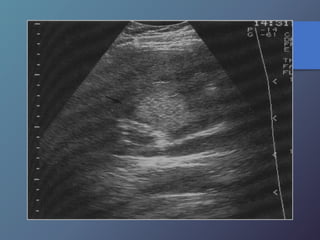

Cirrosis Hepática

Proceso difuso hepático caracterizado

por fibrosis y la conversión de la

arquitectura normal del hígado en

nódulos estructuralmente anormales.

• Redistribución de volumen. Índice

caudado/lob. Der. 0.65.

• Ecoestructura grosera.

• Superficie nodular.

• Nódulos de regeneración.

• Nódulos displásicos.

• Hipertensión portal: Ascitis, esple-

nomegalia, varices.

Características Ecográficas